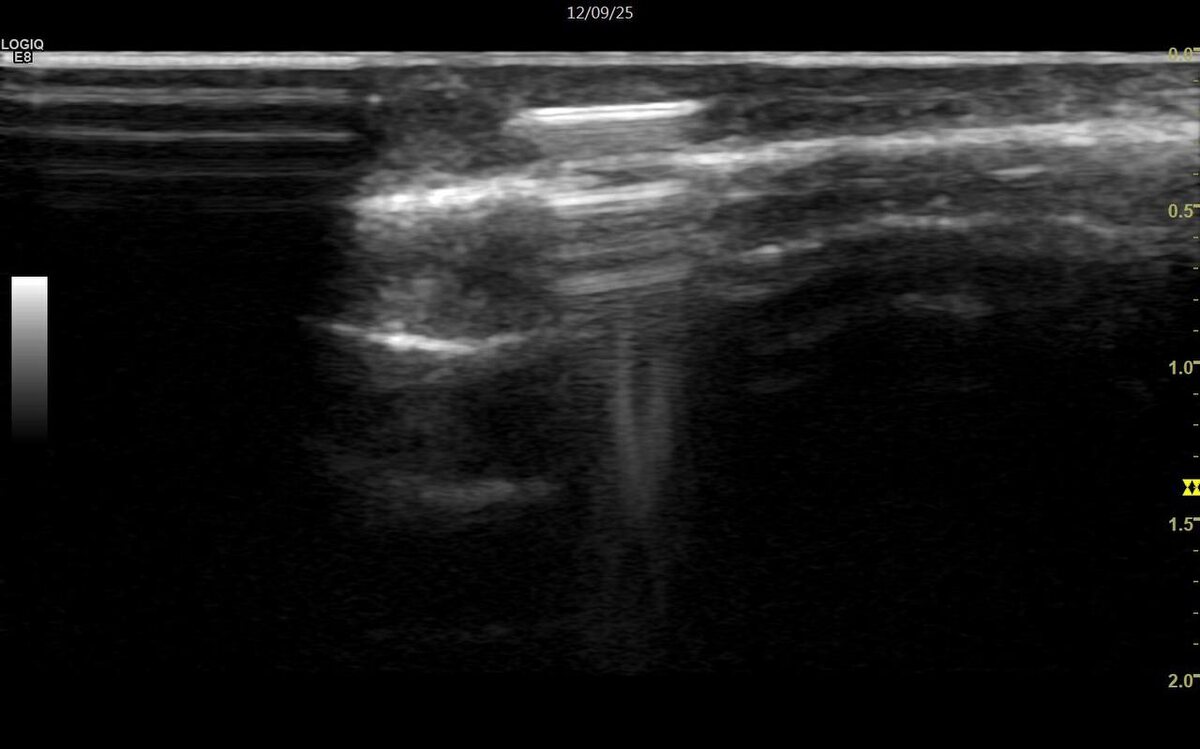

И вот, спустя час и два ведра геля - она, тоненькая полоска в проекции локтевой сумки.

Вот так может выглядеть стекло при УЗ-иссулодании.

"Да, точно, было падение на стекло, но потом вытащили осколки" - вспомнила пациентка.

Но один остался.